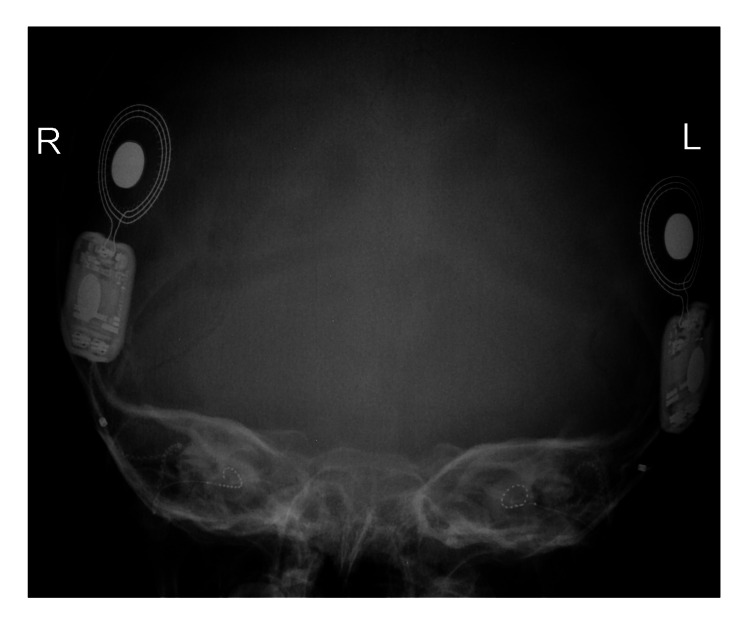

患者被 CI 委員會(huì)確定為雙側(cè)植入的候選者。 在三歲零五個(gè)月大時(shí),進(jìn)行了雙側(cè)同時(shí)人工耳蝸植入(HiRes™ Ultra #D 人工耳蝸,右 HiFocus™ SlimJ 電極和左 HiFocus™ Mid-Scala 電極,Advanced Bionics AG,加利福尼亞州,美國(guó))。 術(shù)后 X 線顯示 CI 陣列有效插入耳蝸內(nèi)(圖 2)。 手術(shù)后第二天開機(jī),并給予兩個(gè) Naida CI Q70 聲音處理器(Advanced Bionics AG,加利福尼亞州,美國(guó))。

An external file that holds a picture, illustration, etc.

Object name is cureus-0014-00000021063-i02.jpg

病例 2 的術(shù)后 X 線顳骨顯示雙耳人工耳蝸電極陣列有效插入